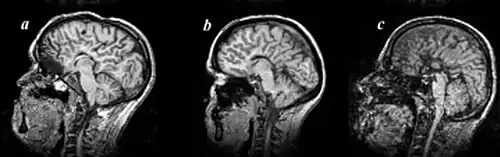

Agenesis of the corpus callosum (ACC) is a rare birth defect in which there is a complete or partial absence of the corpus callosum. It occurs when the development of the corpus callosum, the band of white matter connecting the two hemispheres in the brain, in the embryo is disrupted. The result of this is that the fibers that would otherwise form the corpus callosum are instead longitudinally oriented along the ipsilateral ventricular wall and form structures called Probst bundles.

Callosal disorders can be diagnosed through brain imaging studies or during autopsy.[8] They may be diagnosed through an MRI, CT scan, Sonography, prenatal ultrasound, or prenatal MRI.[1]